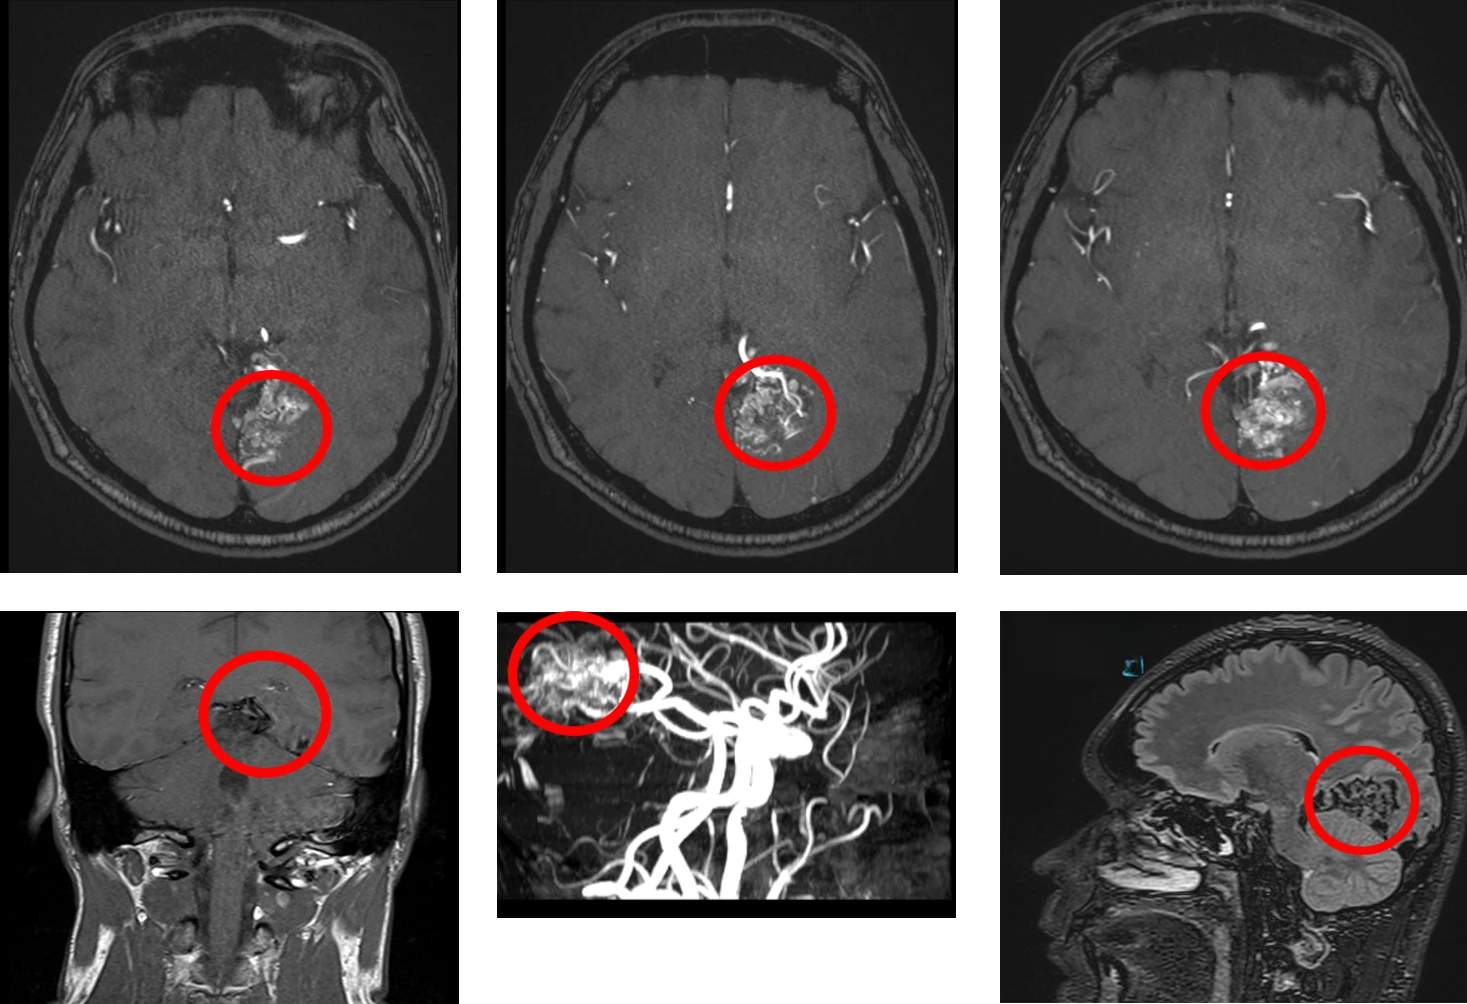

The patient has L occipital arteriovenous malformation (AVM). Stereotactic radiosurgery was performed with good results. The patient still experiences migraine headaches but without aura. He also has a persistent visual field defect due to scarring from AVM.